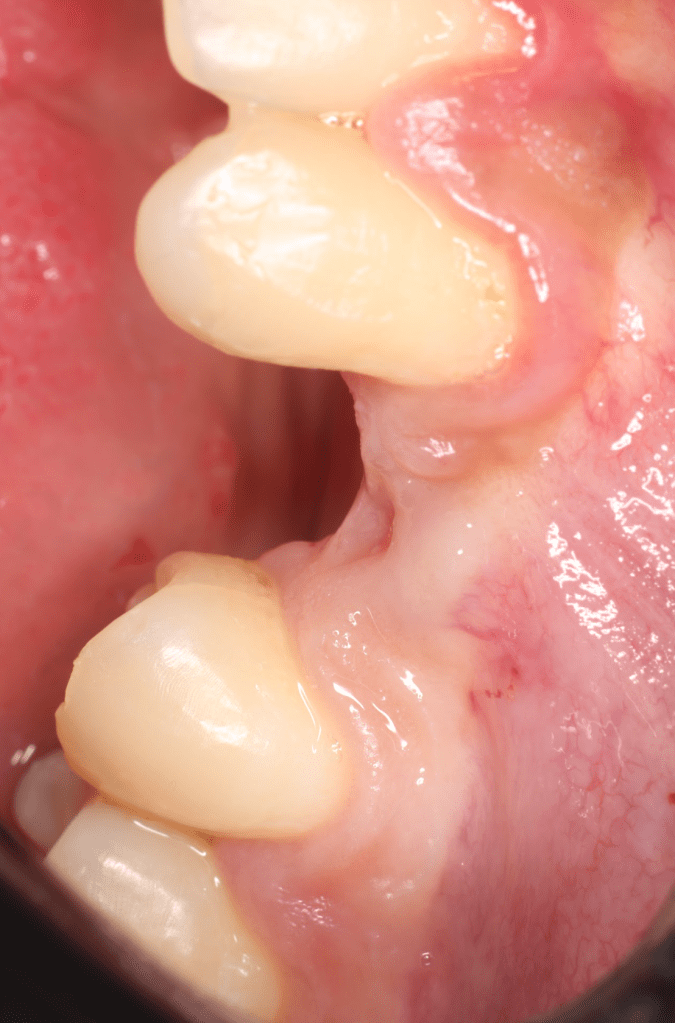

Extrusión quirúrgica